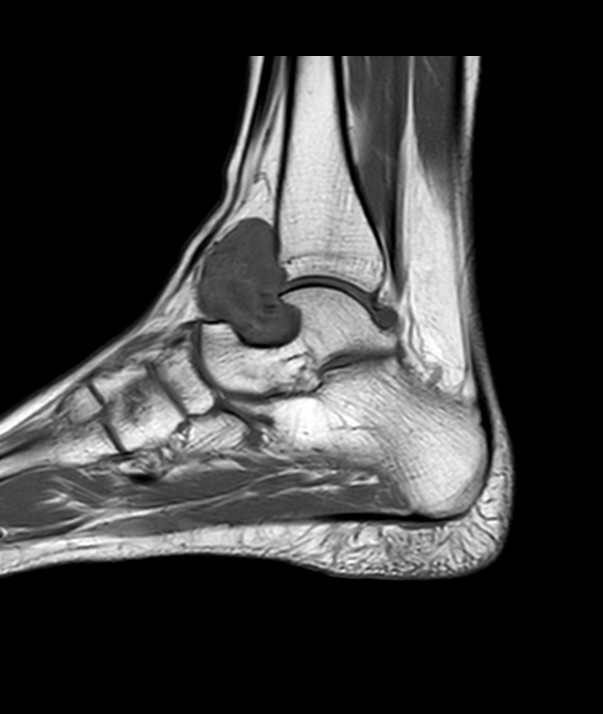

Tenosynovial giant cell tumour

Findings: A well-defined soft tissue mass lesion measuring 3.0 x 3.0 x 5.0 cm is seen just anterior to the right ankle joint. This lesion has heterogeneous T1 and T2 signal intensity and well-defined outer margins showing smooth pressure erosions on the talar neck and distal anterior tibia. No fat component, haemorrhage, or calcifications are seen in it. The lesion shows significant enhancement in the post-contrast study and central degeneration. No bone marrow oedema is seen in the underlying bones. No abnormal ankle joint effusion is seen. The supporting ligaments of the ankle are preserved.

Tenosynovial giant cell tumours are usually benign lesions that arise from the tendon sheath. It is unclear whether these lesions represent neoplasms or merely reactive masses. On imaging, these lesions are commonly demonstrated as localised, solitary, subcutaneous soft tissue nodules, with low T1 and T2 signal and moderate enhancement.

MRI

Not surprisingly, given the histological similarity to PVNS, giant cell tumours of the tendon sheaths also share the same finding on MRI, mainly on account of haemosiderin accumulation.

Signal characteristics

T1: low signal

T2: low signal

T1 C+ (Gd): often show moderate enhancement 6

GE: low and may demonstrate blooming